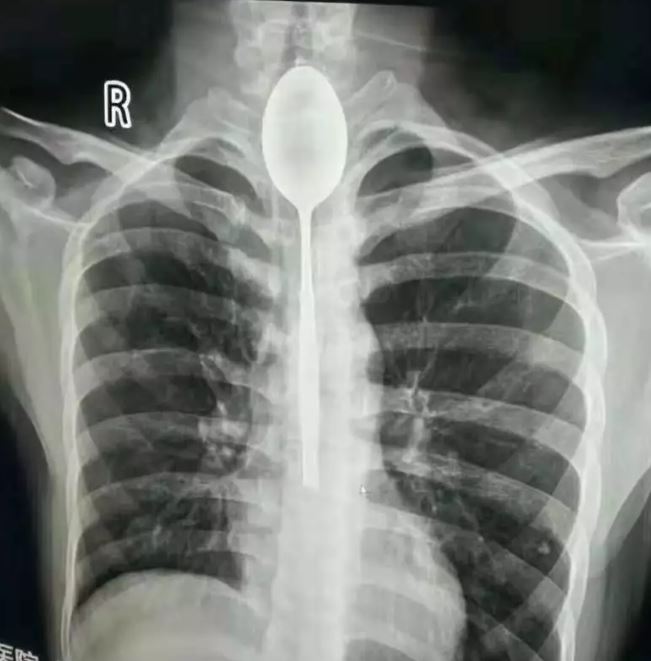

Los doctores que lo atendieron quedaron totalmente sorprendidos cuando se percataron qué le provocaba tanto dolor al paciente: tenía una cuchara de 20 centímetros en su esófago. “Me quedé impactado. Nunca he tenido algo así”, afirmó a Daily Mail el doctor Yu Xiwu.

Los médicos le realizaron una radiografía y determinaron que no era necesario realizar una operación para sacar el cubierto, así que lo sacaron vía bucal. Según un comunicado del recinto de salud, el paciente de 26 años estuvo totalmente anestesiado en el procedimiento que duró un poco más de dos horas.